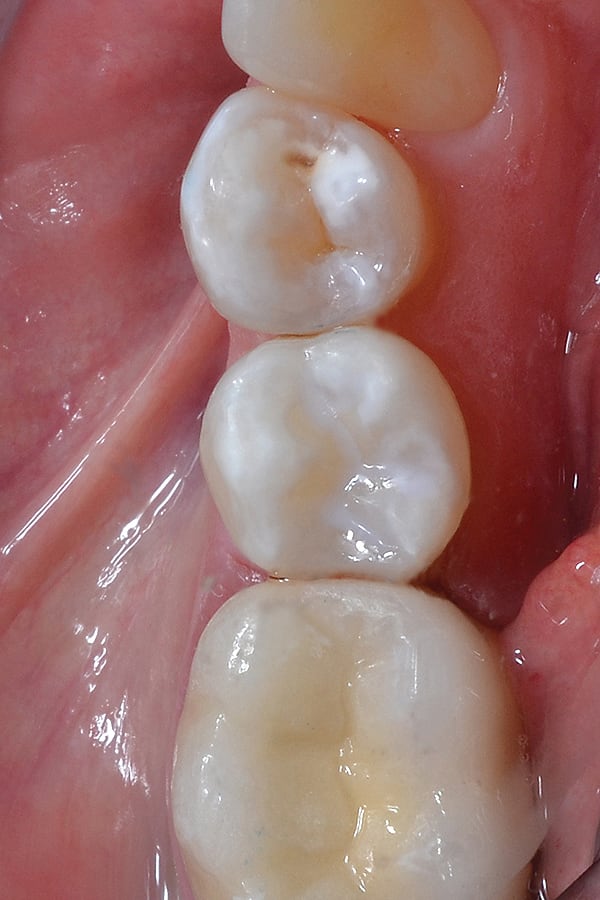

9. The final restoration on tooth No. 29 showing excellent color, contour, and interproximal contact. The restoration was completed efficiently using the DENTSPLY Class II Total Practice Solution, which allowed the author to work faster and still provide an outstanding clinical result.